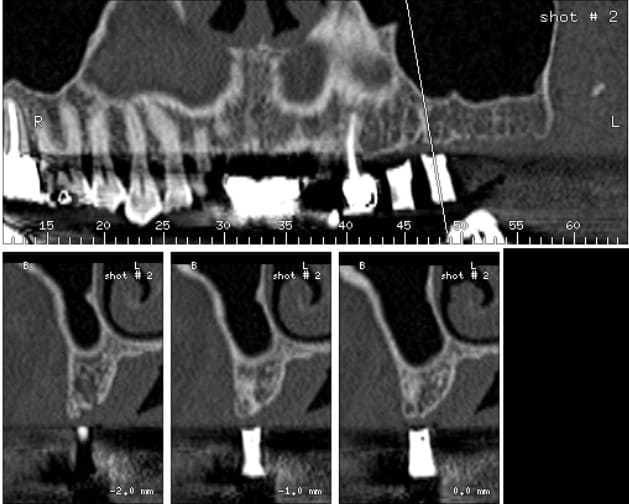

apparement, sur ton image, tu as bel et bien 7 à 8 mm d'os.

donc, tu fores à 7 avec un stop, si tu veux aplanir, tu le fais ensuite.

il me semble que tu as largement la place pour un 8mm et même un 10mm en perforant le sinus avec ou sans summers.

ça me paraît être le cas idéal pour une summers. L'os paraît assez peu dense, tu auras une bonne compaction avec cette technique.

en summers t'as 5 % d'échec s'il te reste plus de 6 mm d'os et 56 % si t'as 4 mm ou moins; à toi de voir ....